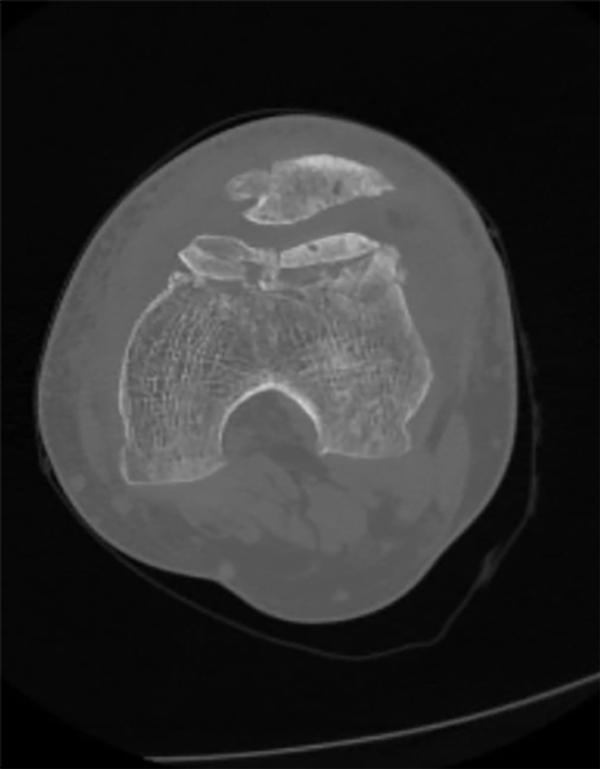

Dado el antecedente quirúrgico, se solicitaron nuevos estudios complementarios en los que se observó una tróclea plana (Dejour C) en TC y radiográficos (figs. 2 y 3). Se decidió realizar revisión de plástica del LPFM con tendón cuadricipital + trocleoplastia con técnica de profundización del sulcus.

Figura 3: TC. Obsérvese secuela de antecedente quirúrgico patelar (plástica de LPFM) y medición de distancia TT/TG.